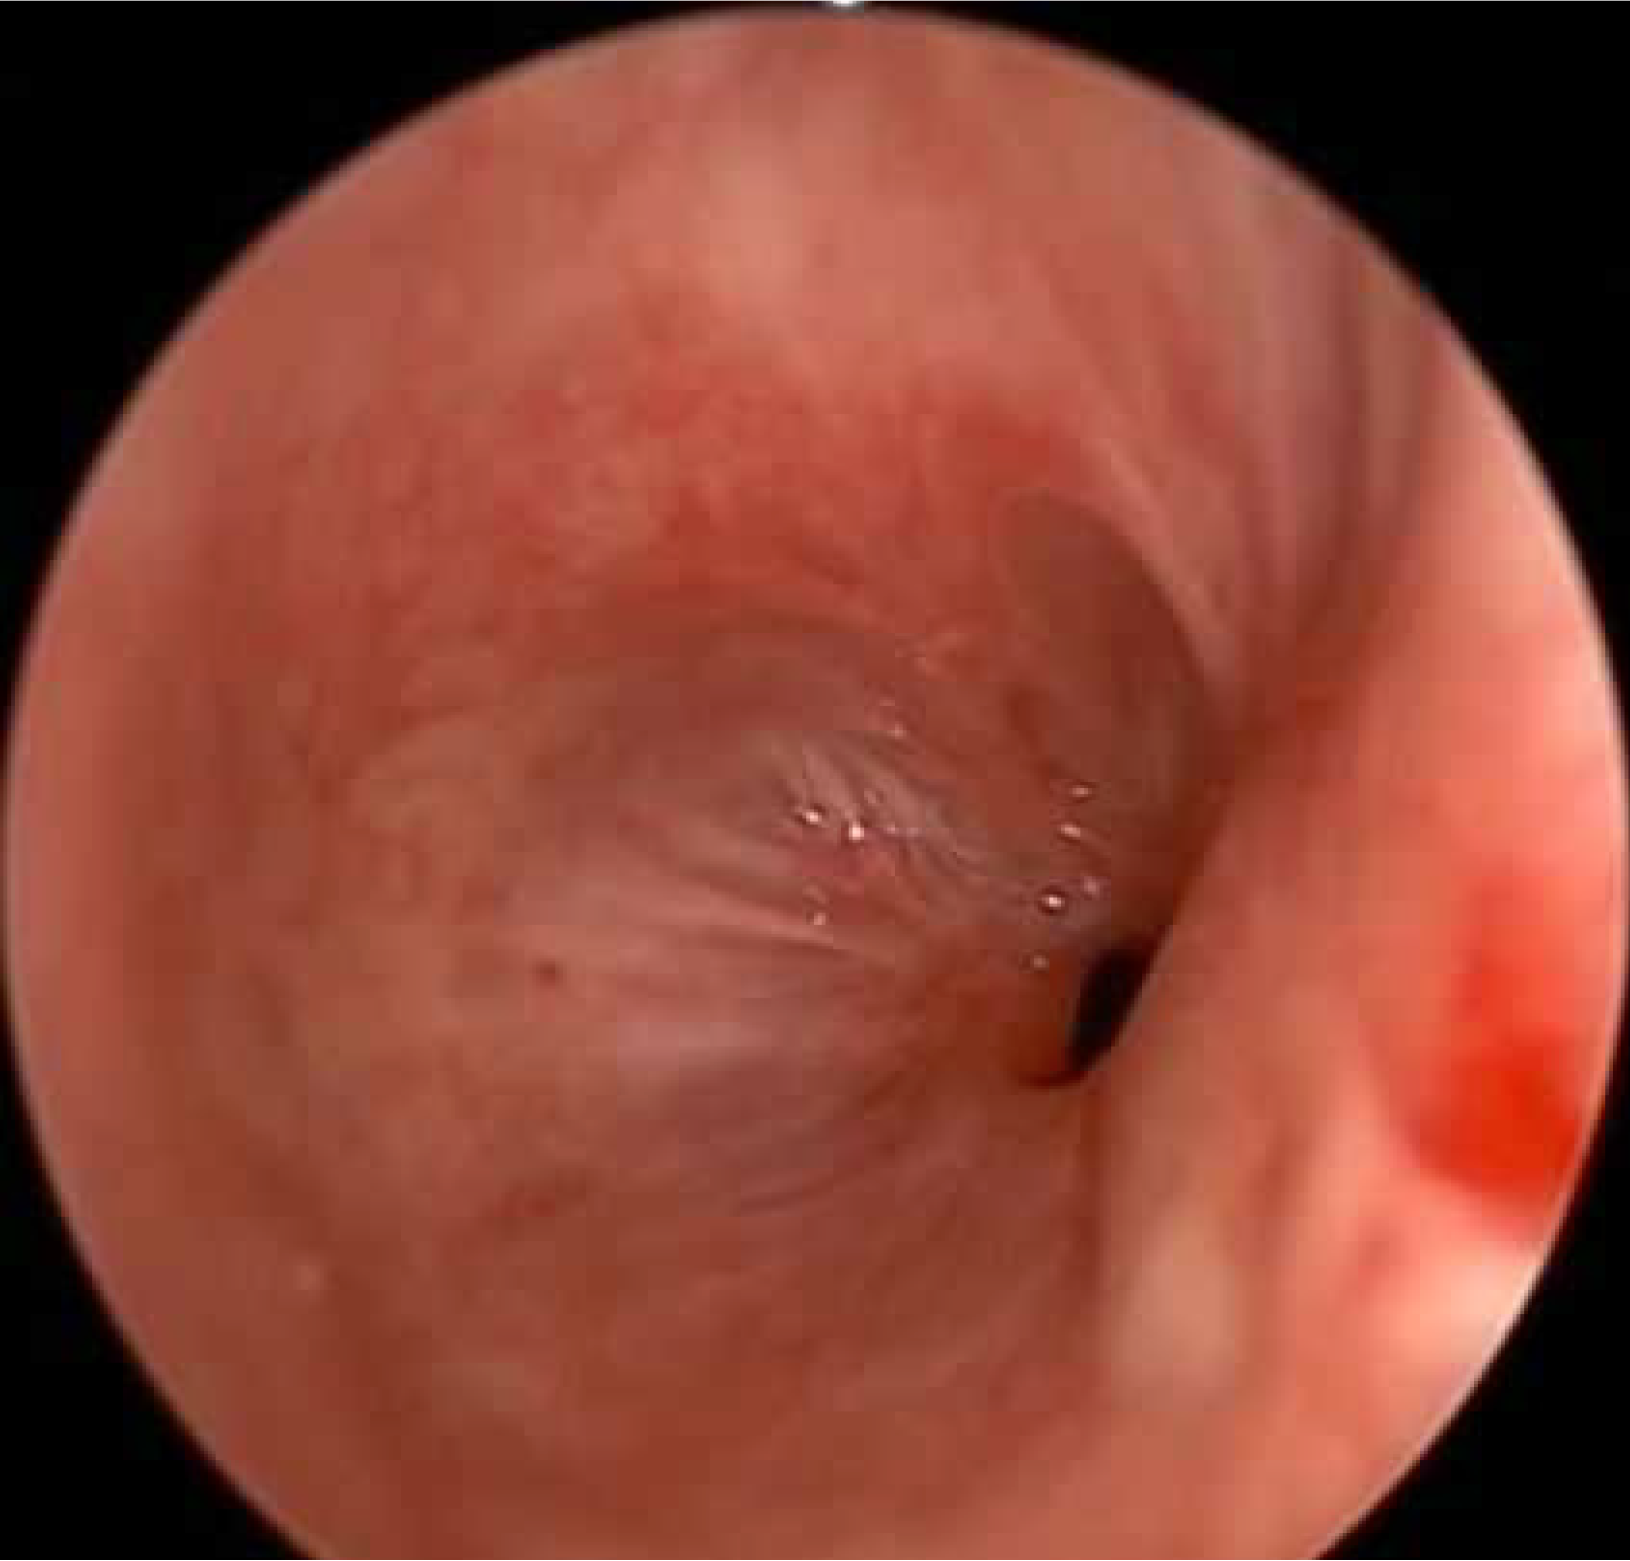

No systemic anticoagulation was administered in the perioperative period, and we did not observe any issues with circuit clotting or ECMO membrane dysfunction. Only one patient developed tension pneumothorax whilst on ECMO, which was unrelated to ECMO. This complication was unrelated to ECMO itself. The cause was tracheal perforation during intubation due to the sharp end of a Tribute endotracheal tube stylet in a patient with severe tracheal stenosis. The situation was recognized promptly and managed appropriately. We did not observe ECMO-related complications. Table 1 summarizes the patients’ data, including demographics, diagnosis, computed tomography (CT) findings, surgical and ECMO procedures, and outcomes. Figures 2, 3, 4 and 5 are examples of airway difficulties in our cohort (Fluoroscopy X-ray, CT scan, and bronchoscopy imaging). Pain and nutritional management were integral parts of patient care. Pain control was achieved using multimodal analgesia, including opioids and sedatives tailored to each patient's needs. Nutritional support was initiated early, with a preference for enteral feeding; parenteral nutrition was used when enteral access was not feasible or contraindicated.